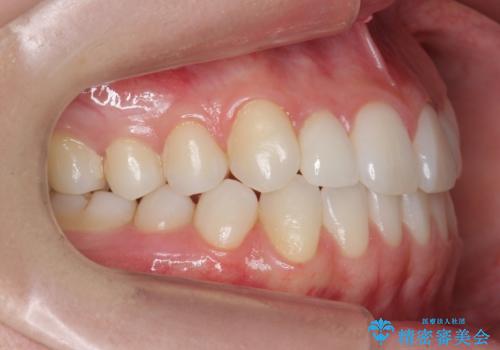

- 前歯のがたつきと小さな歯の形を治したいと来院。

前から2番目の歯が小さく、細くとがった形になっていました。

大きくしようにも、幅が少ない上に、また、内側に入ってしまっているため、矯正治療で前歯を並べてからセラミックでかぶせることにしました。

先に矯正治療をすることで、下の前歯を内側に入れることができ、上の歯のセラミックの幅や厚みを取ることができました。